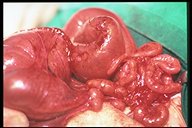

Operative finding of intestinal atresia type III, small mesenteric defect is noted at the atretic site between the disproportioned segment

Operative finding of intestinal atresia type III, moderate mesenteric defect is noted at the atretic site between the disproportioned segment.